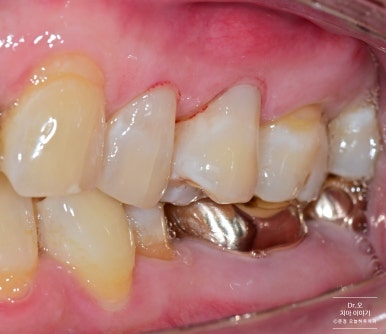

▶ 케이스 3: #24, 25 치아 수복

- 다른 환자분 케이스입니다.

- 좌우 대칭으로 심미성과 기능을 고려한 수복이 이루어졌습니다.

레진 직후 촬영으로 잇몸 자국이 남아 있지만 하루이틀이면 회복됩니다.